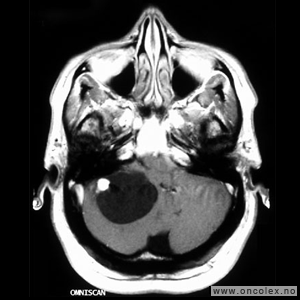

Vestibularisschwannom

Av hjernenervesvulstene er det vestibularisschwannom som er vanligst. Schwannomer kan forekomme på flere hjernenerver, men er i de fleste tilfeller altså lokalisert til balansedelen av hørsels- og balansenerven (åttende hjernenerve). Vestibularisschwannom diagnostiseres vanligvis i 40–50 års alder og er noe hyppigere hos kvinner enn hos menn. Nesten alle vestibularisschwannomer er godartede og vokser langsomt. Hos 5 % av pasientene finner man vestibularisschwannom på begge sider. Disse pasientene har per definisjon nevrofibromatose type 2.